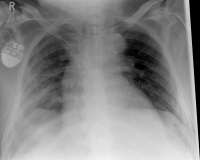

Rippenserie re1

Pneumothorax / tension pneumothorax

In some cases, the sharp rib fragments cause lung or outer chest wall injuries. As a result, air can enter the gap between the lung and chest wall and cause a so-called pneumothorax, which must be treated by drainage.

In rare cases, a so-called tension pneumothorax may develop, which under certain circumstances can also be life-threatening. Due to an injury-related valve mechanism, air from the lungs flows into the gap between the lungs and the chest wall, but can not escape. As a result, the organs are shifted in the chest and concentrated, so that the circulatory function is impaired. It requires, in these cases, an immediate delimbing in the hospital or by an emergency physician.